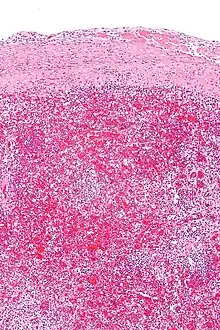

Micrograph of hyaloserositis of the spleen (sugar-coated spleen). H&E stain.

In pathology, hyaloserositis is the coating of an organ with a fibrous hyaline,[1] resulting from inflammation of the serous membrane (serositis) covering the organ.[2]

The spleen is commonly affected and often referred to as sugar-coated spleen.[3] The liver and heart are also sometimes affected and referred to as frosted liver (or sugar-coated liver) and frosted heart respectively.[1]